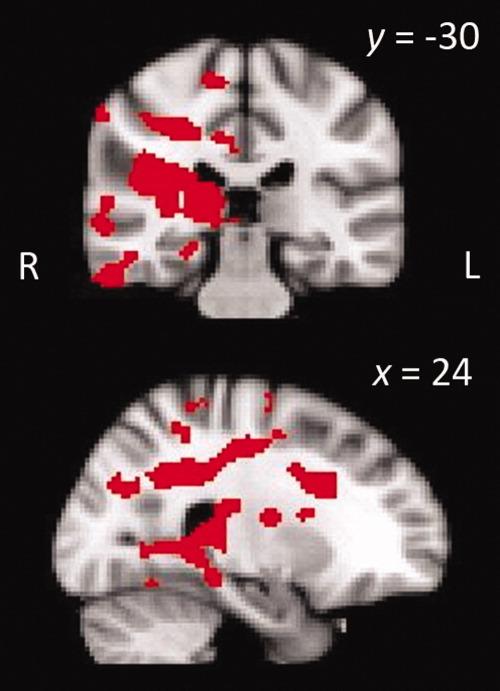

It has been suggested that complex visual discrimination deficits in patients with medial temporal lobe (MTL) damage may be explained by damage or dysfunction beyond the MTL. We examined the resting functional networks and white matter connectivity of two amnesic patients who have consistently demonstrated discrimination impairments for complex object and/or spatial stimuli across a number of studies. Although exploratory analyses revealed some significant differences in comparison with neurologically healthy controls (more specifically in the patient with a larger MTL lesion), there were no obvious findings involving posterior occipital or posterior temporal regions, which can account entirely for their discrimination deficits. These findings converge with previous work to support the suggestion that the MTL does not subserve long-term declarative memory exclusively.

有人认为,内侧颞叶(MTL)损伤患者的复杂视觉辨别缺陷可能是由 MTL 以外的损伤或功能障碍引起的。我们研究了两名遗忘症患者的静息功能网络和白质连接,他们在多项研究中一致表现出对复杂物体和/或空间刺激的辨别障碍。尽管探索性分析显示与神经健康对照组相比存在一些显著差异(更具体地说,在 MTL 损伤较大的患者中),但没有涉及枕后或颞后区域的明显发现,这些区域完全可以解释他们的辨别障碍。这些发现与之前的研究结果一致,支持了 MTL 不仅专门负责长期陈述性记忆的观点。